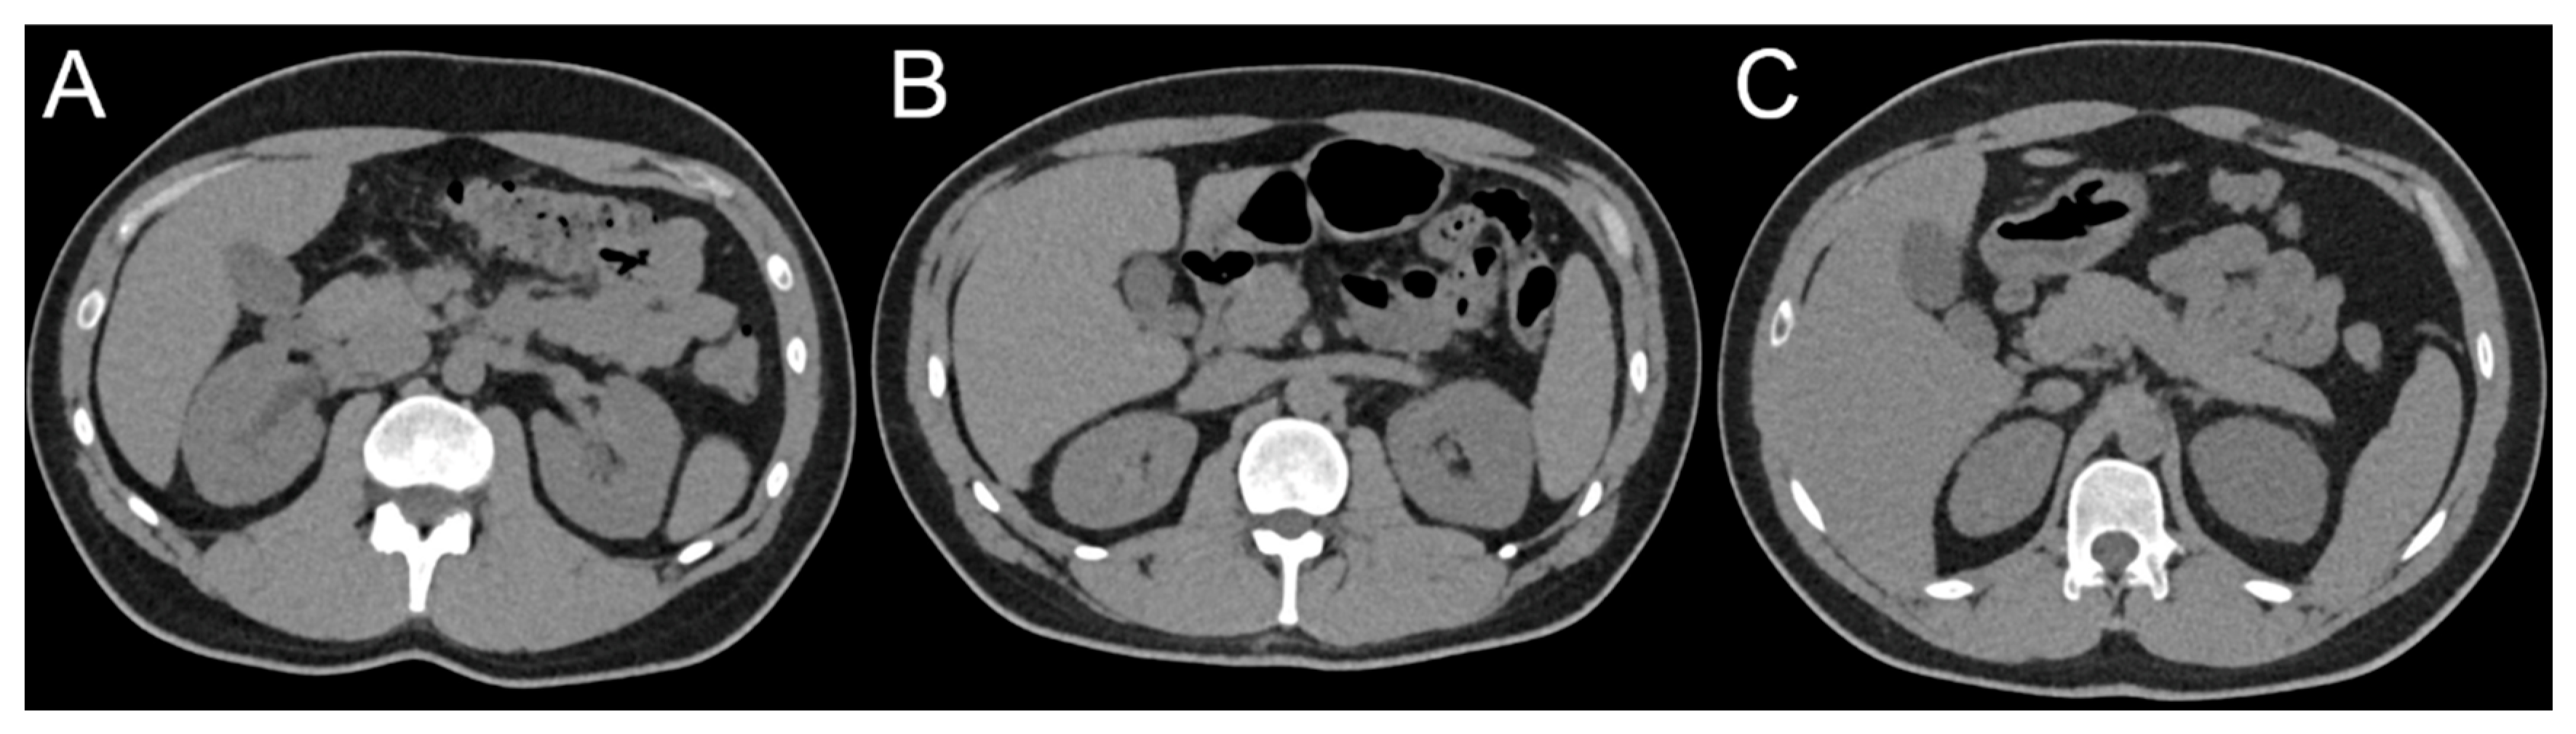

2.2. CT Protocols and Image Acquisition

3.4. Qualitative Image Analysis